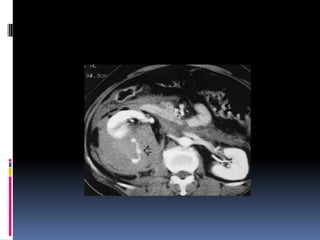

INJURIA PANCREÁTICA  Resultade la compresión de la glándula contra la columna vertebral  Manubrio de bicicleta  Clínica y laboratorio inicialmente inespecíficos

 Signos indirectosde lesión traumática  Agrandamiento difuso  Grasa peripancreática “sucia”  Líquido periglandular  Engrosamiento fascia pararrenal anterior